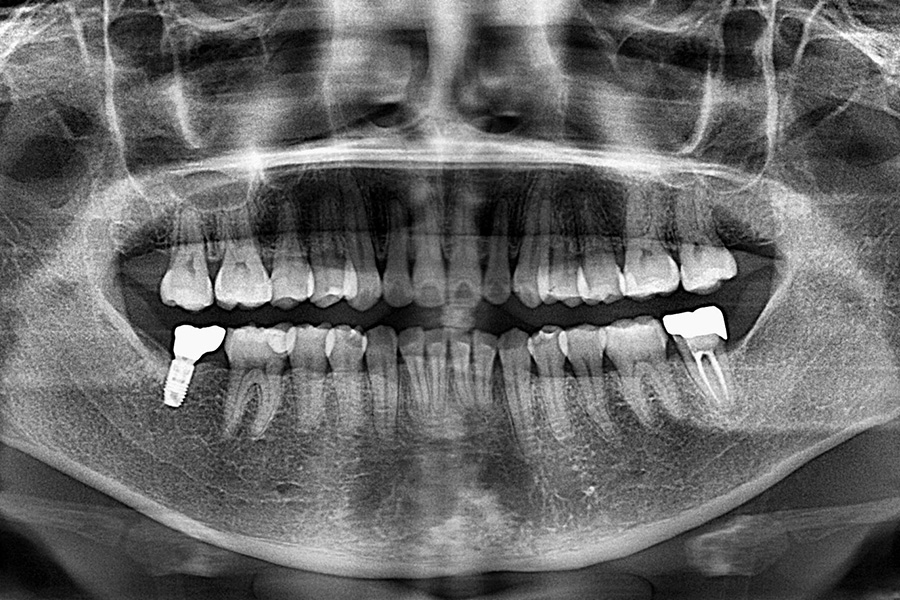

治療後

治療内容 右下7のインプラント治療(1本)